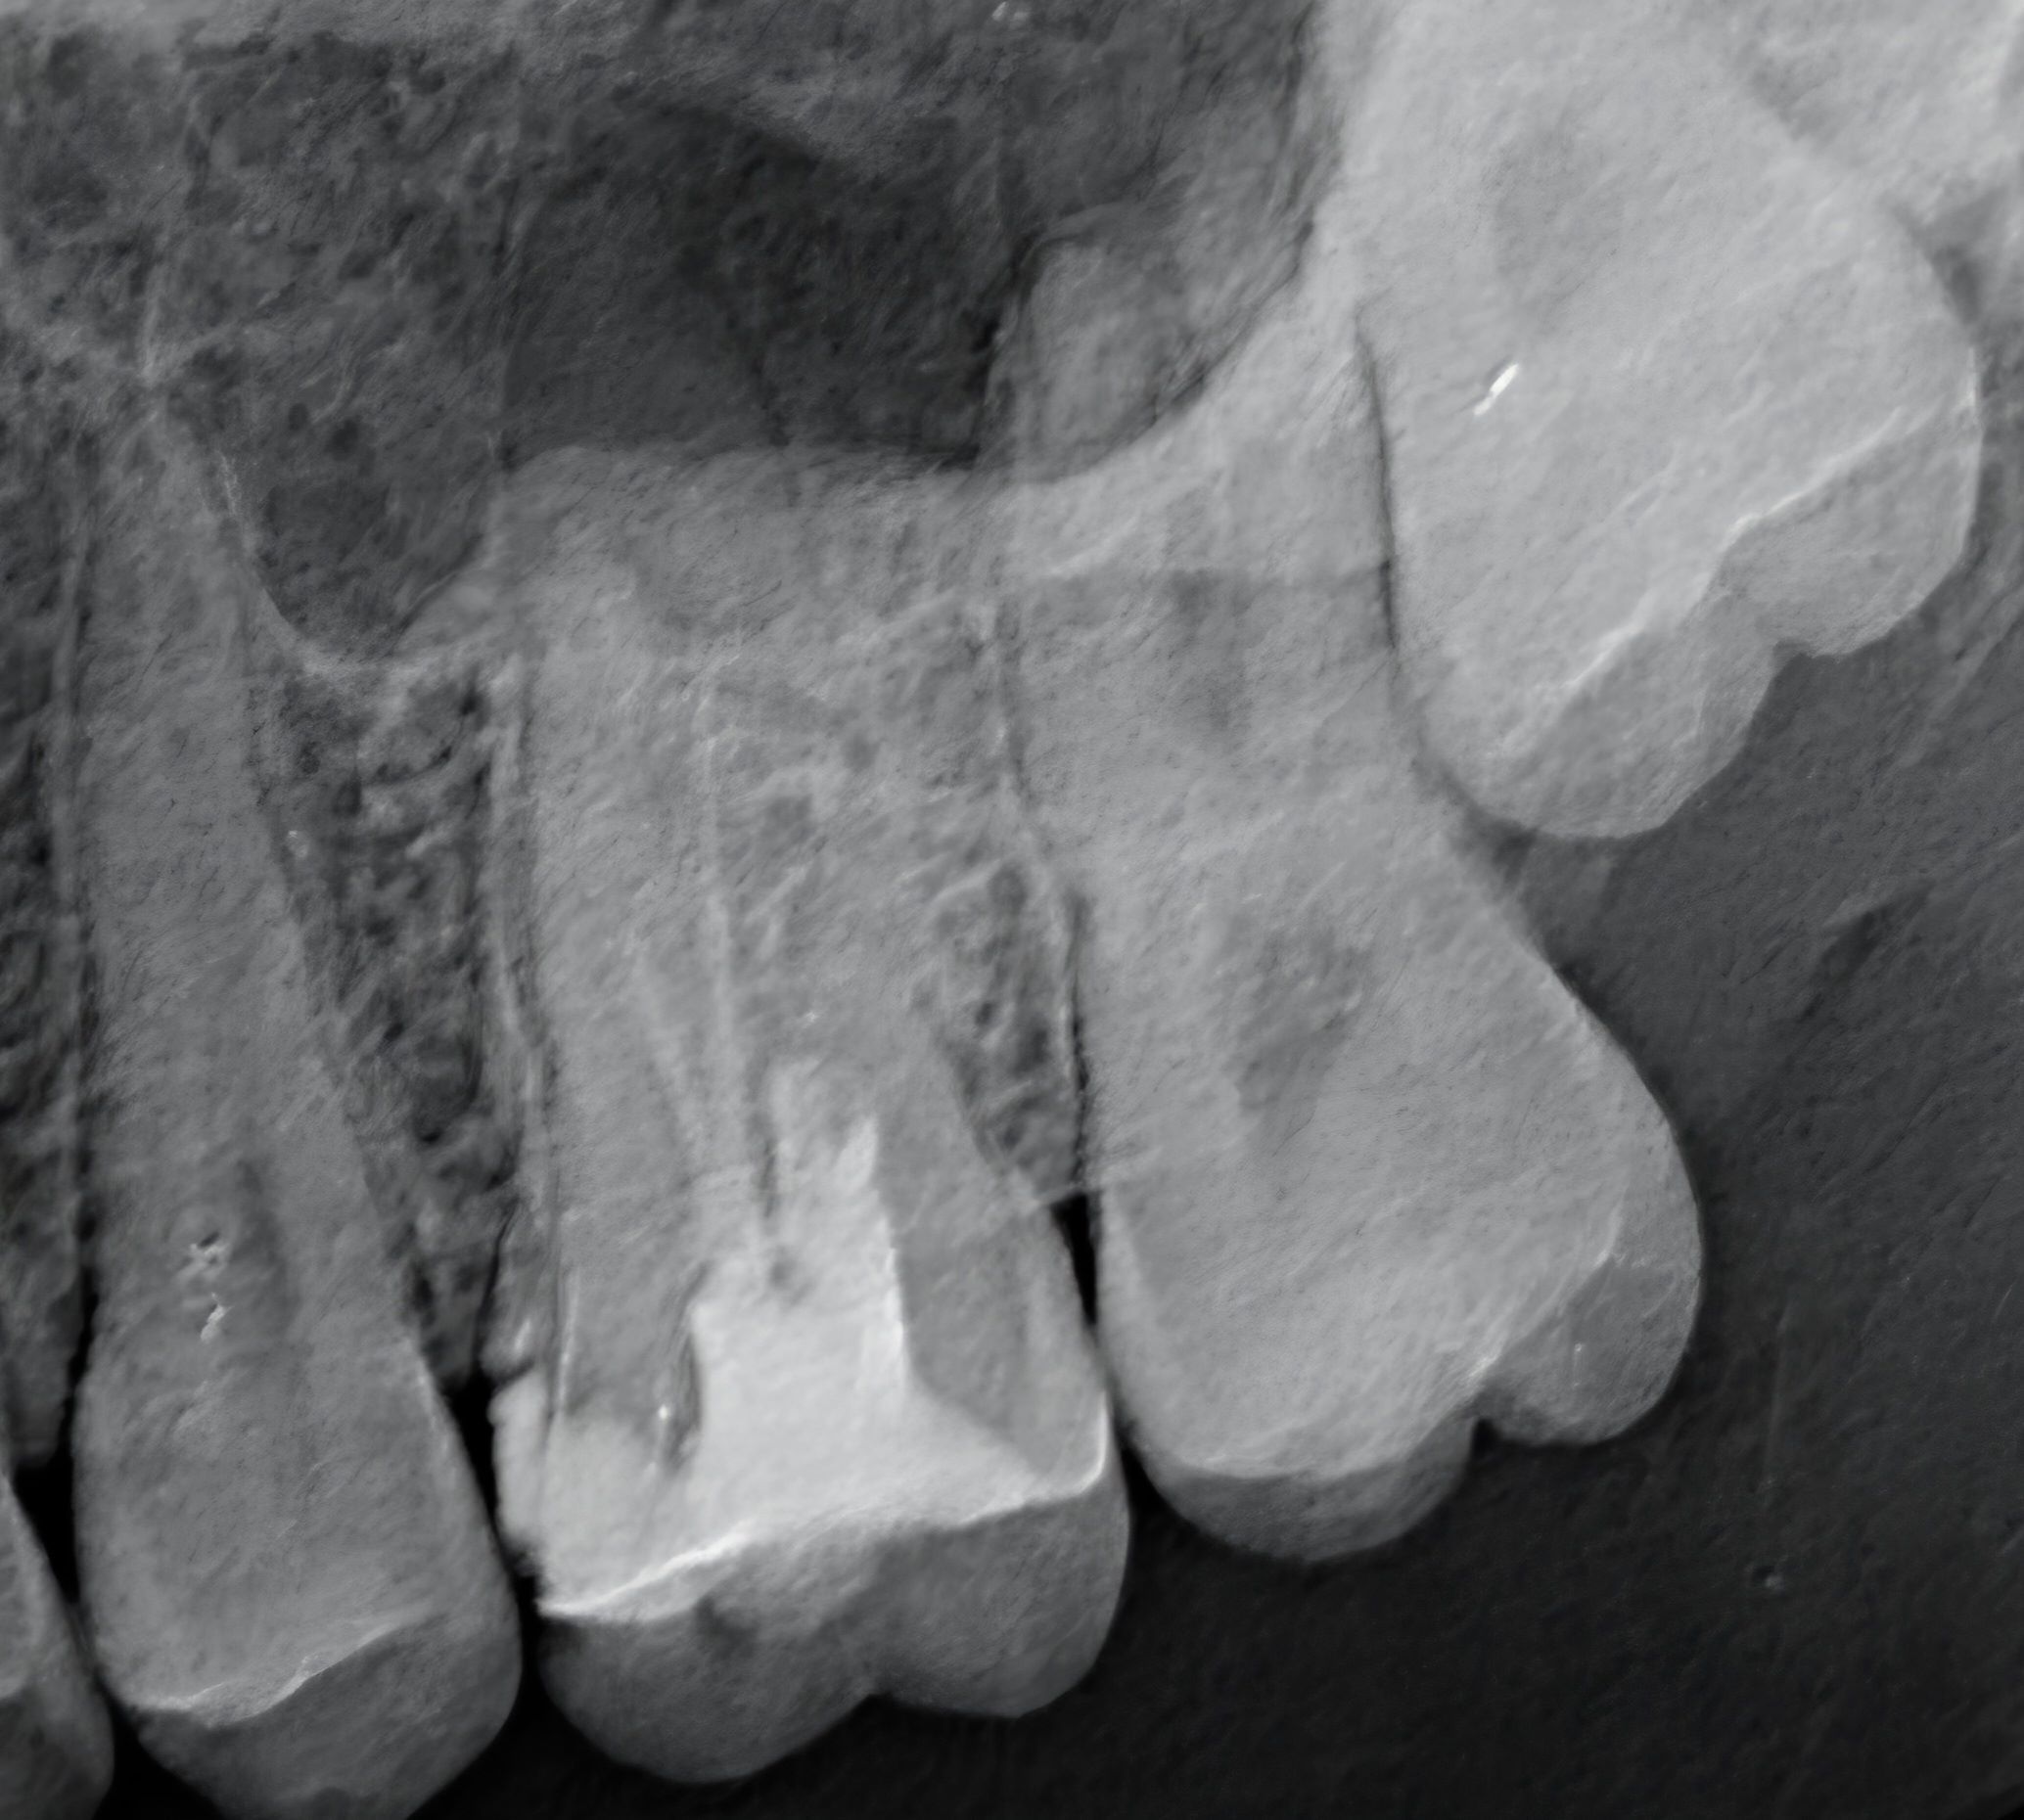

retroalveolarni snimak - POJEDINAČNI SNIMAK ZUBA

Retroalveolarni snimak zuba je precizan rendgenski snimak jednog ili nekoliko zuba, koji prikazuje koren zuba, kost oko zuba, i okolne strukture. Koristi se za dijagnostiku karijesa, procese na korenu zuba i za kontrolu endodontskog lečenja.

1 000,00 rsd